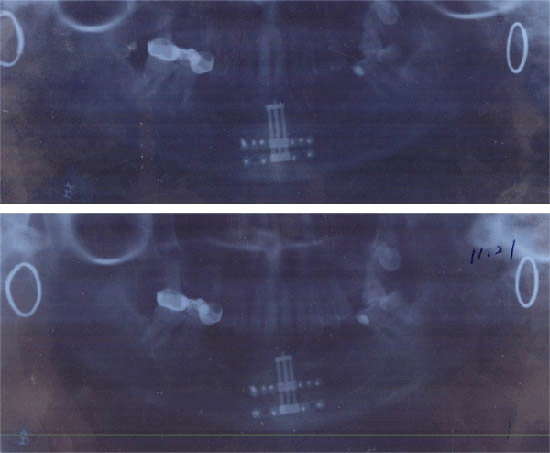

杨××,女,54岁,99年11月底因口底癌,在我院行右侧根治性颈扩清+口底癌扩大切除术+5+5的下颌骨的方块切除术+双侧颊膜瓣口底修复术。术后经过1年多的临床观察,病情稳定。患者要求义齿修复,因其下颌骨前部缺失,已低于唇,舌侧软组织,所以修复很困难,需增加牙槽嵴高度。2000年11月8日全麻下行垂直牵引器植入术。经过术后7天间歇期,于11月14日每天1次牵引升高移动骨段,于11月3日牵引结束,共升高12MM,已达到术前设计要求,经过8周的稳定期后,经X线片检查见骨间隙内新能生成良好,移动骨段稳定,牙槽明显恢复。经过半个月的软组织恢复。于3月末给预铸造活动义齿修复,其面型及咀嚼功能均得到了比较理想的恢复。